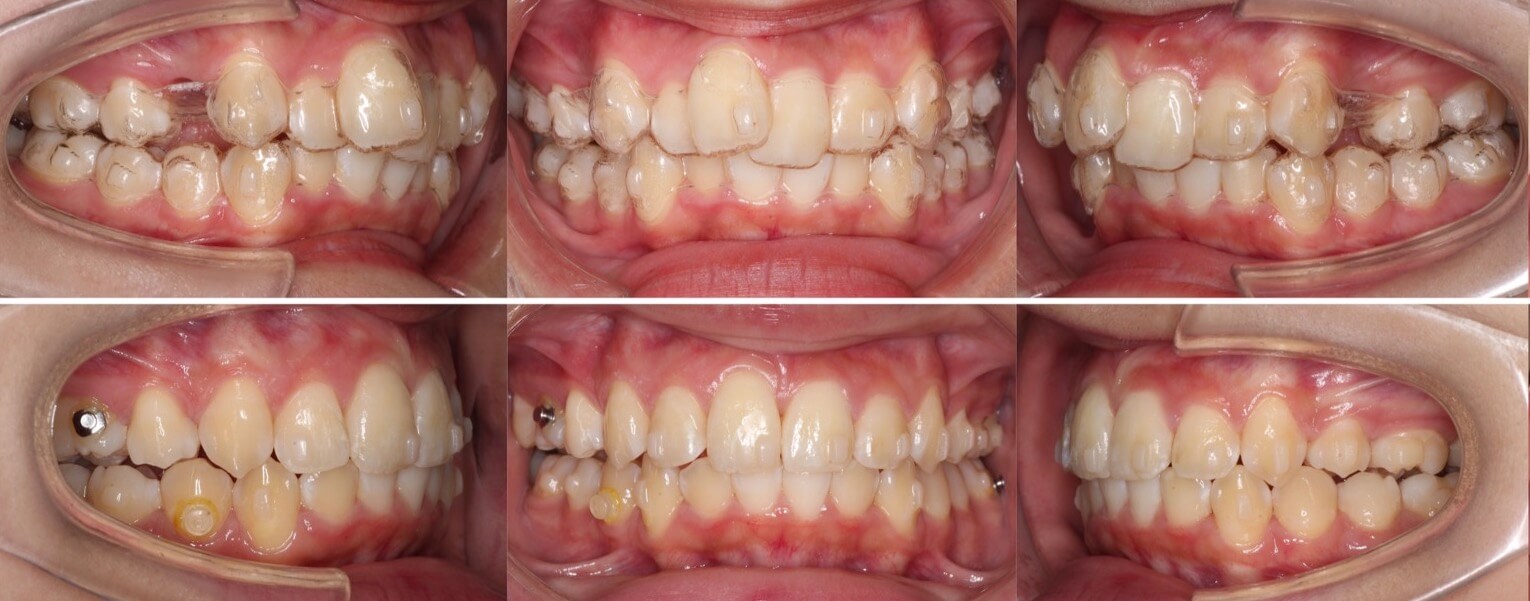

20代男性・マウスピース型矯正装置・上抜歯

マウスピース型矯正治療に向いている典型的な上のみの抜歯症例です。このようなケースは治療期間も短く終了できます。

<症例概要> 難易度★★★☆☆

主訴:上の前歯の前突

年齢・性別:20代男性

住まい:千葉県習志野市

症状:上顎前歯唇側傾斜・叢生・右6番交叉咬合・正中線不一致

治療方針:上顎抜歯空隙閉鎖・下顎歯列拡大・IPR

治療装置:マウスピース型矯正装置(アライナー装置)

抜歯:上左右4番(計2本)

治療期間:1年7か月

アライナー枚数:60+20ステージ(1週間交換)

リテーナー:上下フィックスタイプ+クリアタイプ

治療費用:990,000(税込)

代表的副作用:痛み・治療後の後戻り・歯根吸収・歯髄壊死・歯肉退縮

▶︎その他の副作用

【治療シミュレーション】

上はゆっくりと抜歯空隙を閉鎖しています。

臼歯の交叉咬合を治すために、下の歯を順番に後方移動させています。

※マウスピース型カスタムメイド矯正歯科装置は完成物薬機法対象外の矯正装置であり、医薬品副作用被害救済制度の対象とはならない可能性があります。